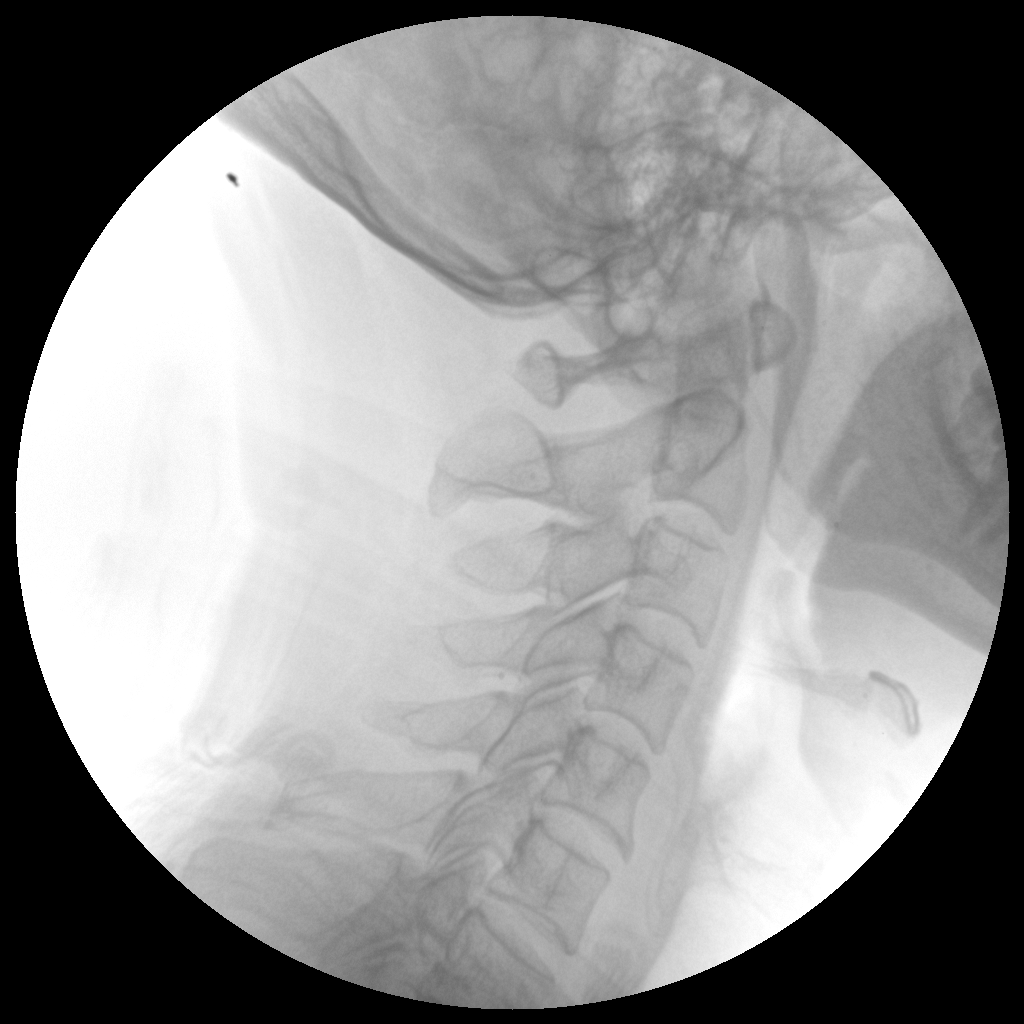

Clinical picture

临床图片